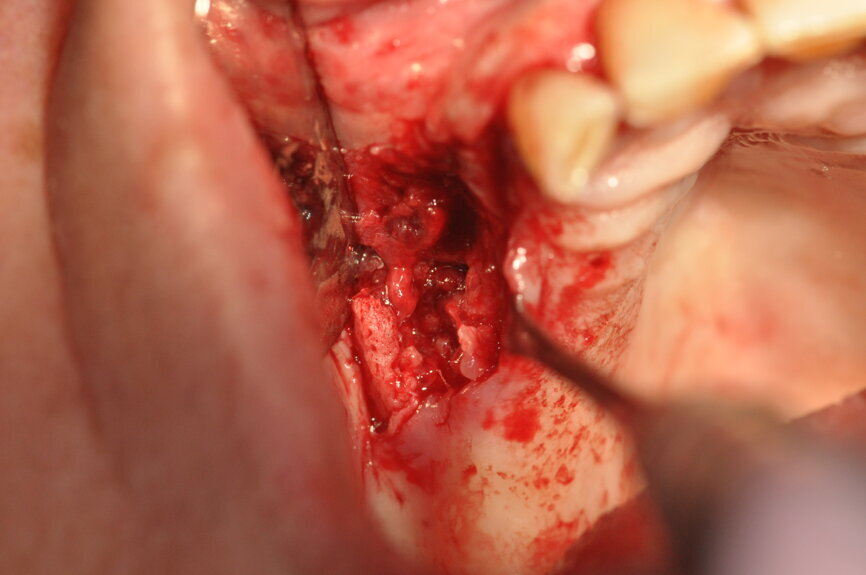

Ryc. 1-3_Stan przed leczeniem: 3. Defekt kostny, stan po utworzeniu płata w celu uzyskania wglądu w pole zabiegowe.